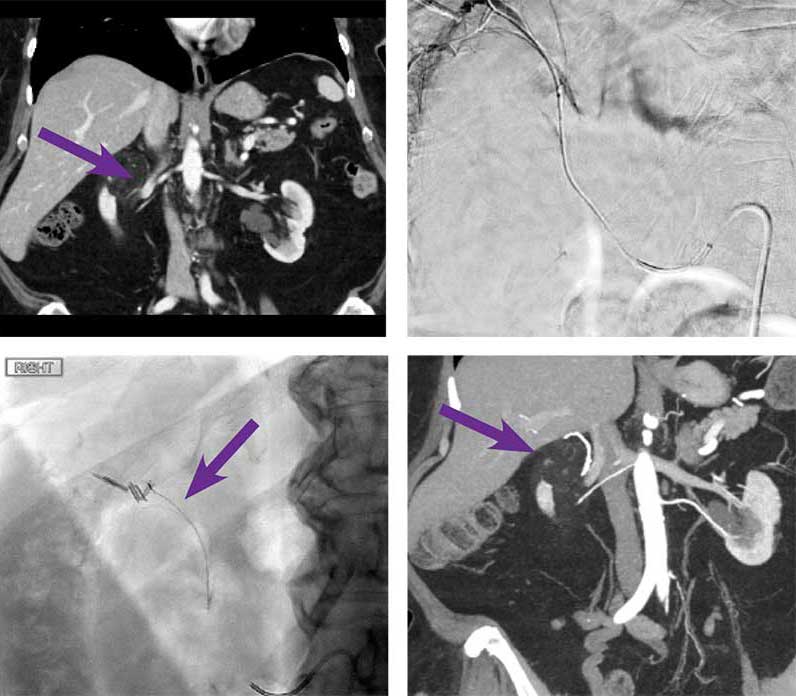

Upper pole angiomyolipoma (AML) embolization

Courtesy of Dr. Mikin Patel I University of Chicago

75-year-old female with right upper pole AML. Lesion was incidentally found when scanning for generalized abdominal pain.

Intervention used

Using a 5F SIM1 catheter, the right renal artery was selected, and angiogram was performed. There was a small vertically oriented artery arising from a superior segmental arterial branch that courses superior to the renal parenchyma in the expected location of the angiomyolipoma seen on recent CT. Using a RenegadeTM STC Microcatheter, the small vertically oriented artery that courses beyond the renal parenchyma was selected and selective angiogram was performed. No renal parenchymal staining was seen. No arterial venous shunting was also observed. 0.2 cc of Obsidio Embolic deployed into 1 mm diameter vessel. Post embolization angiogram showed nonopacification of the occluded vessel with sparing of the remaining renal vessels and good perfusion to the remainder of the kidney.

Outcome

Repeat CT at 6 weeks demonstrating interval decrease in size of the AML from 6.2 cm to 5.2 cm.